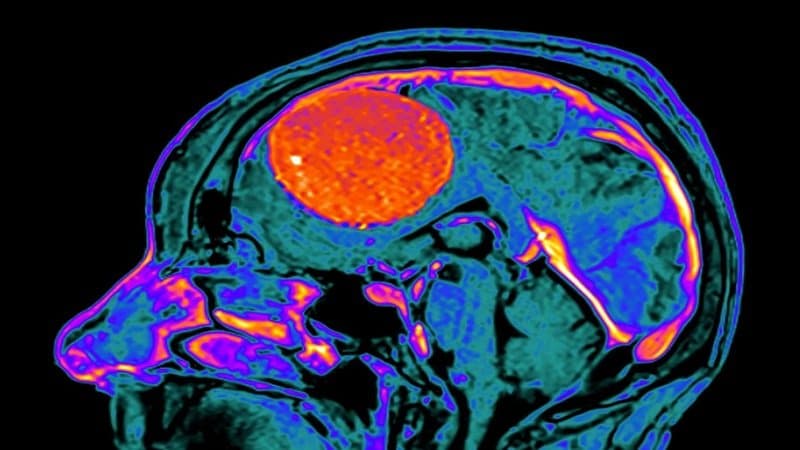

U màng não lành tính sống được bao lâu không có một con số cố định cho mọi trường hợp. Đây là khối u phát triển từ màng não và đa số tiến triển chậm. Nếu được phát hiện sớm và xử trí phù hợp, người bệnh có thể sống lâu dài như người bình thường. Để đánh giá chính xác cần dựa trên đặc điểm khối u và phương pháp điều trị cụ thể.

Tiên lượng sống của bệnh nhân bị u màng não lành tính khá khả quan. Hơn 90% người trưởng thành từ 20 – 44 tuổi có thể sống ít nhất 5 năm sau chẩn đoán, và nhiều trường hợp sống thêm hàng chục năm. Kết quả tốt nhất thường gặp ở những người bị u lành màng não đã được phẫu thuật cắt bỏ hoàn toàn khối u.

Vậy mổ u màng não lành tính sống được bao lâu? Với người được phẫu thuật, tỷ lệ sống sau 3 năm ước tính khoảng 93.4%, cao hơn so với khoảng 88.3% ở nhóm không phẫu thuật. Tuy nhiên, tỷ lệ sống có xu hướng giảm theo tuổi cao, ở nam giới, u màng não lành tính có kích thước lớn, người da đen và một số nhóm dân số nhất định.